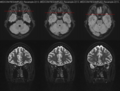

MRT des Sehnervs (axiale und koronale Schnittbilder)